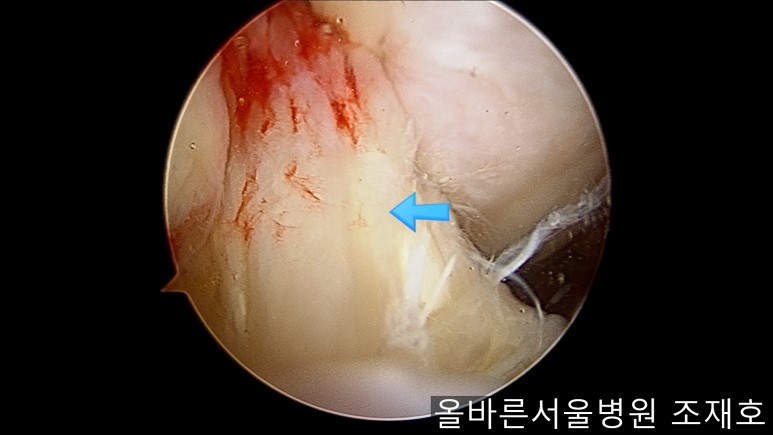

前方十字韧带处没有覆盖滑膜的粘液样变性的外观及稳定性无异常。

image_7703305051519375935910.jpg

与内侧对照,外侧的软骨及软骨板无损伤。

image_2513816991519375935901.jpg